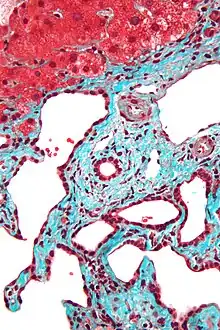

Micrograph of a bile duct hamartoma. Trichrome stain. Intermediate magnification Micrograph of a bile duct hamartoma. Trichrome stain, high magnification

Micrograph of a bile duct hamartoma. Trichrome stain, high magnification Low magnification micrograph of a bile duct hamartoma. Trichrome stain.